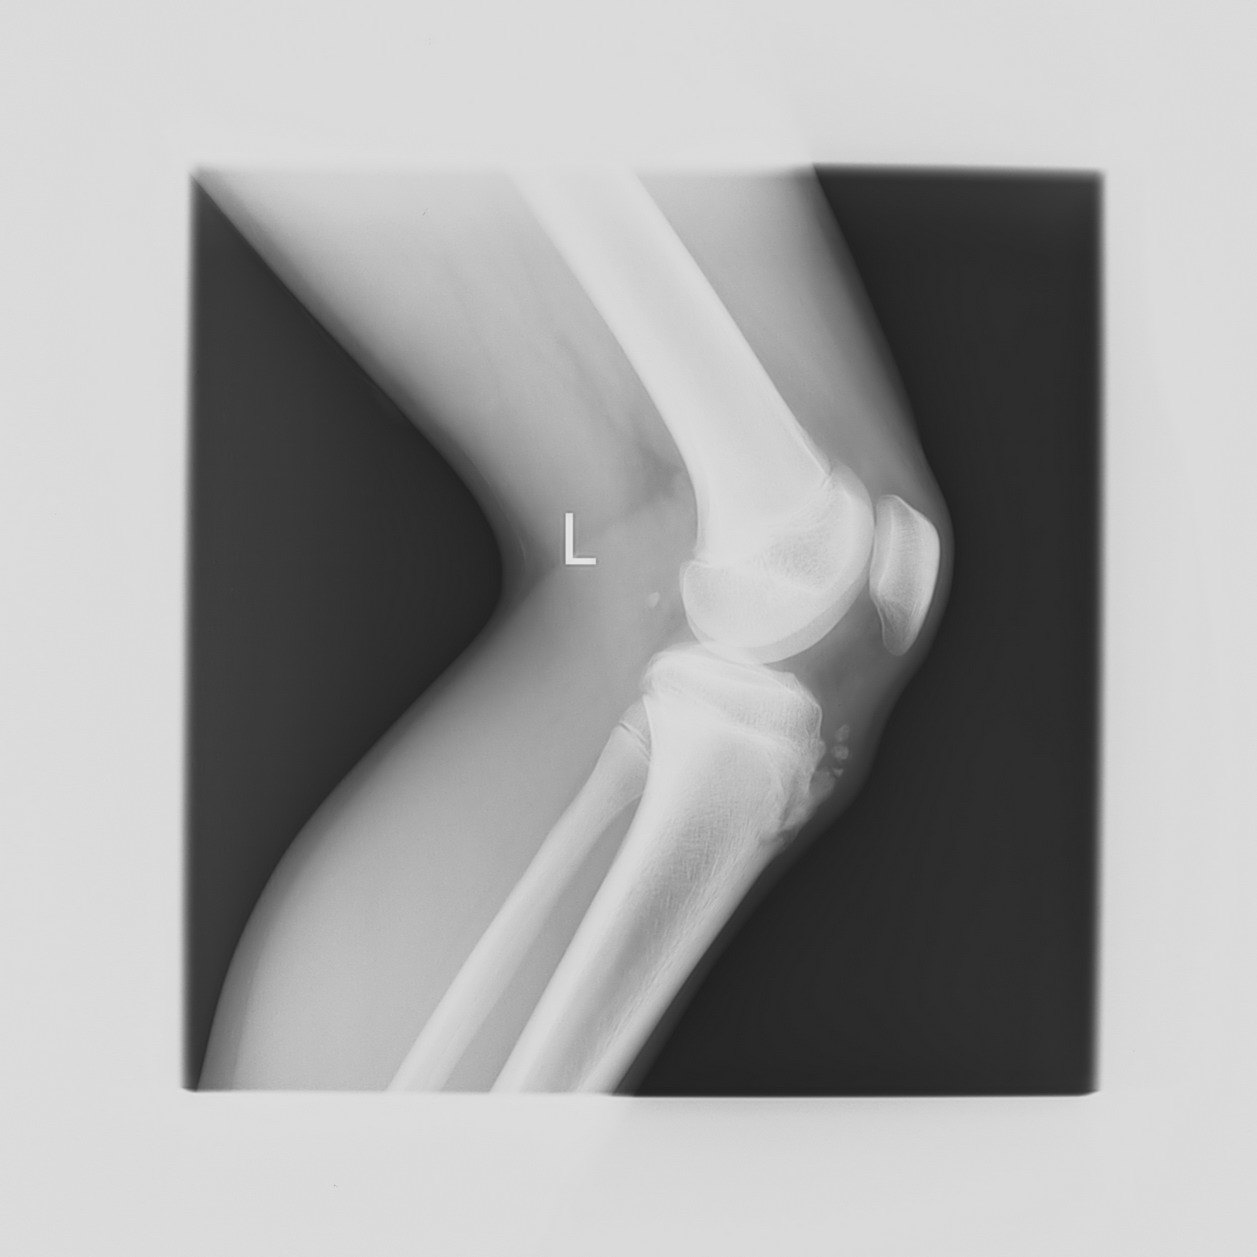

以下是引用qc80012345在2008-5-3 18:26:00的发言:[br]胫前结节缺血性骨软骨炎。

以下是引用宇宙ct在2008-5-3 19:16:00的发言:[br]胫前结节缺血性骨软骨炎